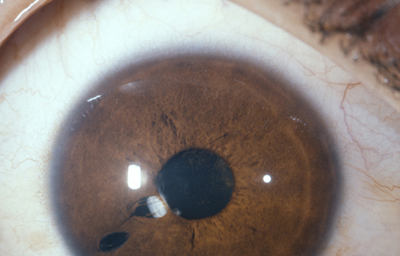

Agujeros en el Iris (dehiscencia y diastasis del Iris)

Dehiscencia: Se entiende por dehiscencia la presencia de pequeños agujeros accesorios y/o hendiduras, ademas de la verdadera pupila

Archivo Fotográfico Dr. Francisco Barraquer

Archivo Fotográfico Dr. Francisco Barraquer

Diastasis: Significa la presencia de agujeros en la raíz del Iris parecidos a una Iridodiálisis

Diastasis del Iris: en un caso de Atrofia Esencial del Iris (Síndrome ICE)

Archivo Fotográfico Dr. Francisco Barraquer